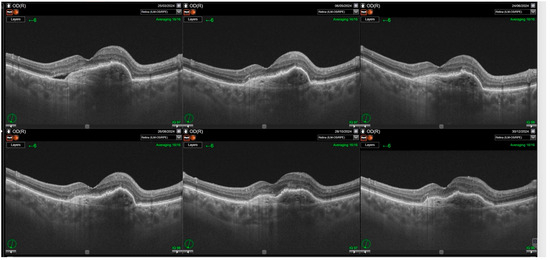

Purpose: To evaluate anatomical and functional outcomes after switching from aflibercept to faricimab in patients with neovascular age-related macular degeneration (nAMD) with suboptimal response. Methods: This retrospective study included 72 eyes of 66 patients with nAMD previously treated with intravitreal aflibercept using a treat-and-extend regimen. Indications for switching included persistent retinal fluid, pigment epithelial detachment (PED), lack of best-corrected visual acuity (BCVA) improvement, or inability to extend treatment intervals beyond four weeks. Patients received three monthly loading doses of faricimab followed by individualized 8- to 16-week dosing. Follow-up comprised six visits over a mean of 8.5 ± 1.4 months. Outcomes included BCVA (logMAR), retinal morphology (subretinal fluid—SRF; intraretinal fluid—IRF; pigment epithelial detachment—PED), central subfoveal thickness (CST), and treatment interval changes. Results: Switching to faricimab led to significant short-term anatomical improvement, primarily reduction in subretinal fluid (p < 0.0001), with maximal effect during the loading phase. Resolution of SRF was significant at the end of the follow up; however, IRF changes were transient and not sustained beyond three months. PED reduction reached borderline significance (p = 0.0455). CST decreased during the loading phase (p < 0.0001) but returned to baseline thereafter. BCVA improved only after loading (p = 0.0287) but not at final follow-up. Treatment intervals were extended by a mean of ~2 weeks (p < 0.0001), increasing in 80% of eyes. Eyes with fewer prior injections and better baseline BCVA achieved superior final visual outcomes. Conclusions: Switching to faricimab provides short-term anatomical benefits and treatment-interval extension without sustained visual gain. Functional improvements tended to be greater in patients with fewer injections and shorter treatment duration prior to switch. Full article

Show Figures

Figure 1